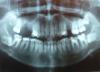

spring23 Опубликовано 1 апреля, 2011 Поделиться Опубликовано 1 апреля, 2011 Уважаемые стоматологи, помогите, пожалуйста, составить план лечения. Мне 41 год, я лечу зубы в основном в бюджетной поликлинике и даже нахожусь там на диспансерном учете, но обычно лечить там начинают, когда уже пол зуба развалиться, а в остальных случаях говорят «ничего страшного», так что вся надежда на вашу консультацию. Если можно, перечислите, что мне следует сделать с зубами в порядке уменьшения срочности и важности.Отдельные вопросы по протезированию:1) Справа : пятёрка удалена 3 года назад. Возможно ли, ставить здесь имплант, нужен ли при этом синуслифтинг и какой? Если не ставить имплант (боюсь осложнений или, что не приживется и деньги будут потеряны), то имеет ли смысл здесь ставить мост? Знаю, что многие жалуются на то, что под коронками зубы гниют и разваливаются. Вот и думаю не получится ли так, что через несколько лет, а может и через год, я из-за моста потеряю и опорные зубы?2) Слева: 5ка удалена 2 года назад, 6ка – месяц назад ( корень был в гайморовой пазухе, , т.к. рентген пазух не выявил гайморита, то врач, проводившая удаление решила не направлять меня на операцию и соустье зарастает само, при удалении повреждена альвеола). Возможно ли после всего выше перечисленного здесь устанавливать импланты, не опасно ли в моём случае? Что Вы думаете о бюгельном протезировании? То, что это съемный протез меня не пугает, наоборот мне нравиться, что можно все почистить и соблюсти гигиену. Только вот из прочитанного в интернете, я не поняла: если крепление на замках и зубы с замками покрыты коронкой, то это ведь уже не съемная конструкция, и значит таже проблема что и у моста (под коронки может набиваться еда)? Ссылка на комментарий

juli63 Опубликовано 1 апреля, 2011 Поделиться Опубликовано 1 апреля, 2011 восьмые зубы удалять-все. каналы в 36,37 перелечить, там же по показаниям вкладка, коронка, 47тоже; 46,45,35- сделать качественное восстановление. Ссылка на комментарий